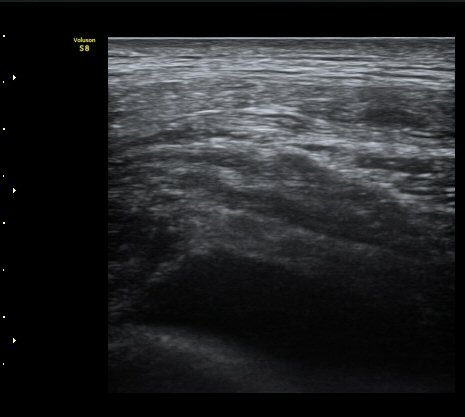

°¥ºñ»À ÇÇÁú°ñ ¿¬°á¼º ¼Ò½Ç°ú ¾à°£ÀÇ ÀüÀ§, ¿¬ºÎÁ¶Á÷ ºÎÁ¾ÀÌ °üÂûµÊ (loss of cortical continuity and soft tissue swelling of rib)  »çÁø 2